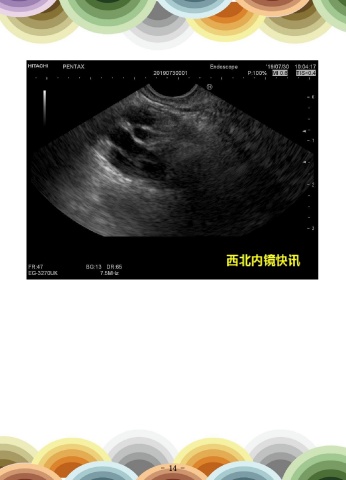

一例乳头及胆总管末端排石改变

患者男,59岁,因“全身皮肤巩膜黄染伴右上腹疼痛3周余”就诊。于当地医院行

CT示:肝内胆管轻度扩张,胆囊稍大。超声内镜示:胆囊结石并胆囊炎;乳头及胆总管

末端排石改变。患者在全麻下行腹腔镜胆总管切开取石术,胆囊切除术,手术顺利。